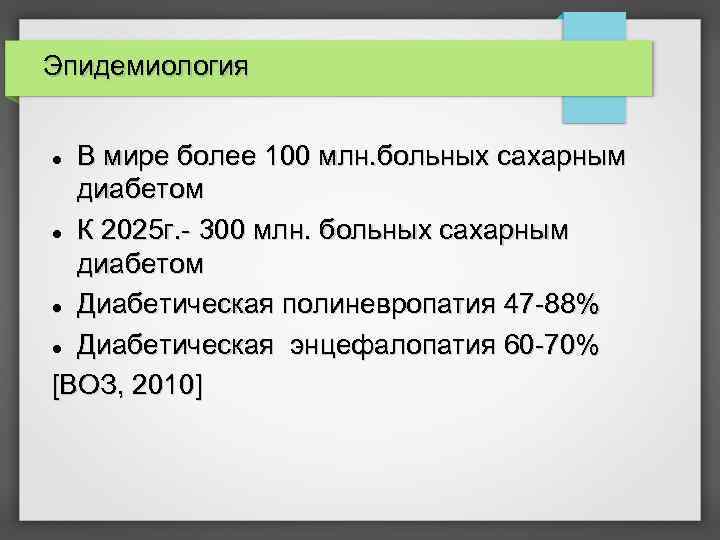

Эпидемиология В мире более 100 млн. больных сахарным диабетом К 2025 г. - 300 млн. больных сахарным диабетом Диабетическая полиневропатия 47 -88% Диабетическая энцефалопатия 60 -70% [ВОЗ, 2010]